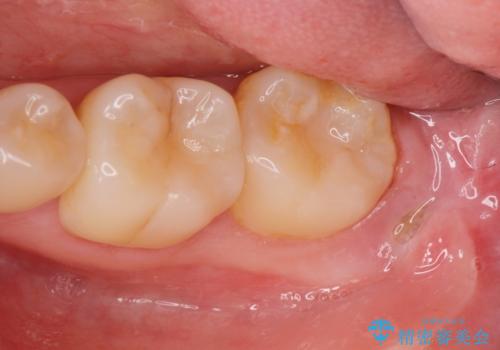

親知らず・埋伏歯の抜歯掲載症例数39件

最新 親知らず・埋伏歯の抜歯症例